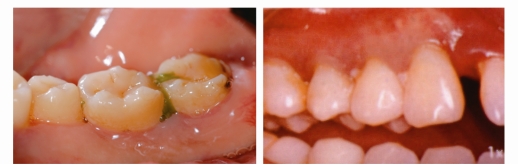

反复的牙龈肿痛溢脓

有些患者牙龈反复“长包”,并且有黄色的脓液流出,这就是牙周炎症导致的“牙周脓肿”。

食物嵌塞

牙周炎症导致牙龈萎缩、牙缝增大,食物嵌塞也就随之而来。